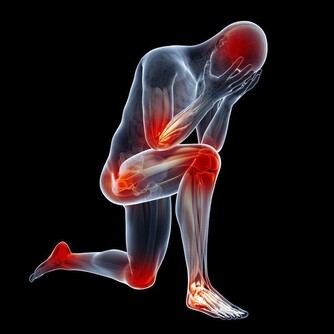

從症狀來看,肺炎也有輕微和嚴重等不同症狀,其中包括:

咳嗽、有痰

發燒

出汗或發冷

呼吸急促

胸部疼痛

乏力、身體疲勞

食慾下降

噁心、嘔吐